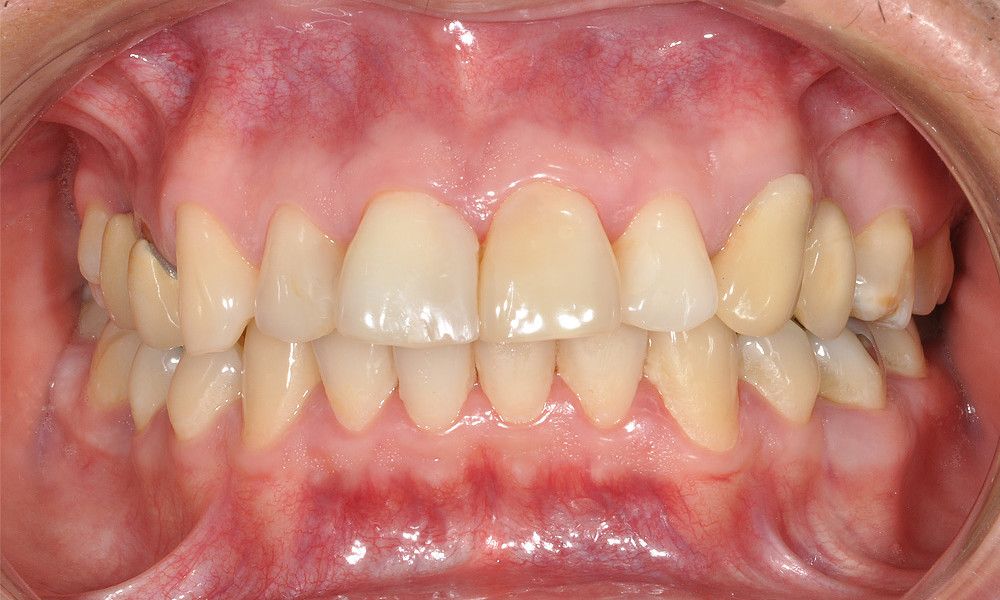

Reporte del Caso: Paciente sexo masculino, 36 años, con diagnóstico de esquizofrenia y trastorno bipolar en tratamiento. Consulta por el recambio de dos prótesis fijas plurales (PFP) de reemplazo de dientes 4 y 13 con pilares en piezas 3, 5, 12 y 14 mediante rehabilitaciones unitarias de los dientes pilares y reemplazo mediante implantes en zonas edéntulas.

El estudio imagenológico evidencia una pérdida ósea severa en altitud y grosor, situación que complejiza la colocación de un implante. Se analizan alternativas de tratamiento y se opta por una vestibuloplastía mediante autoinjerto conectivo de mucosa palatina que se reposiciona sobre la zona del defecto óseo. Además se realiza retratamiento de ambas PFP, ahora en zirconia, por motivos estéticos y oclusales. Se realizan controles posteriores para evaluar la respuesta gingival a la vestibuloplastía.